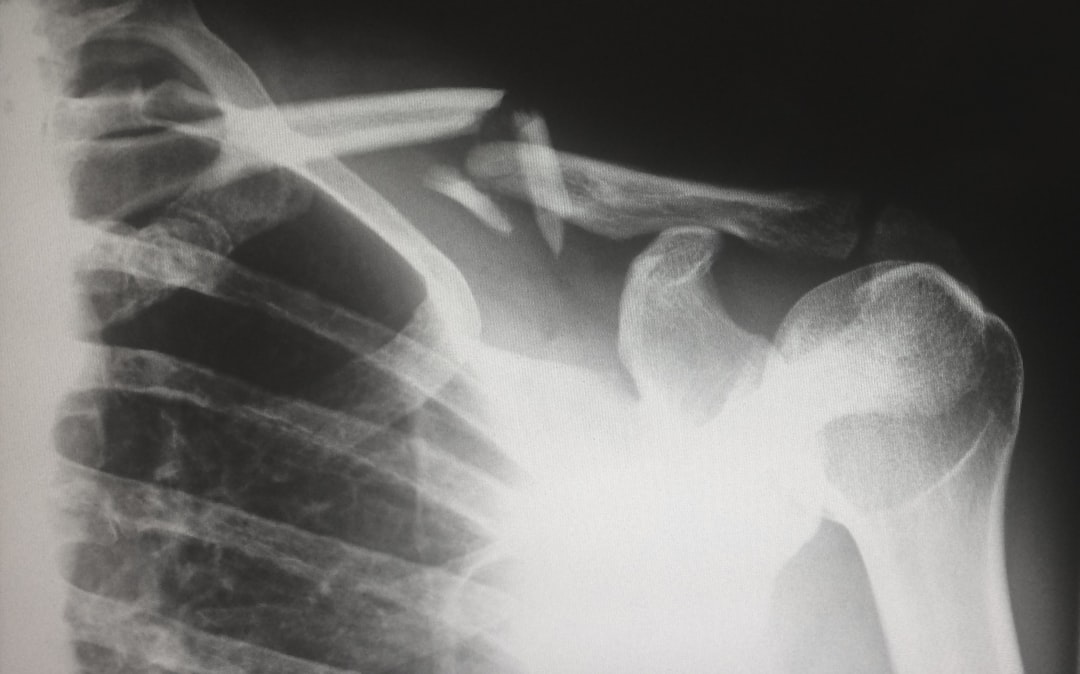

특히 단백뇨가 나오면 신장에 문제가 있을 수 있으니 주의해야 해요. 세 번째로는 가슴 엑스레이(흉부 X-ray)가 포함되는데, 폐 질환이나 심장 질환을 조기에 발견할 수 있어요. 그리고 마지막으로, 꼭 기억해야 할 것이 체중과 신장 측정이에요.

가슴 엑스레이 폐 및 심장 질환 발견 1년에 한 번